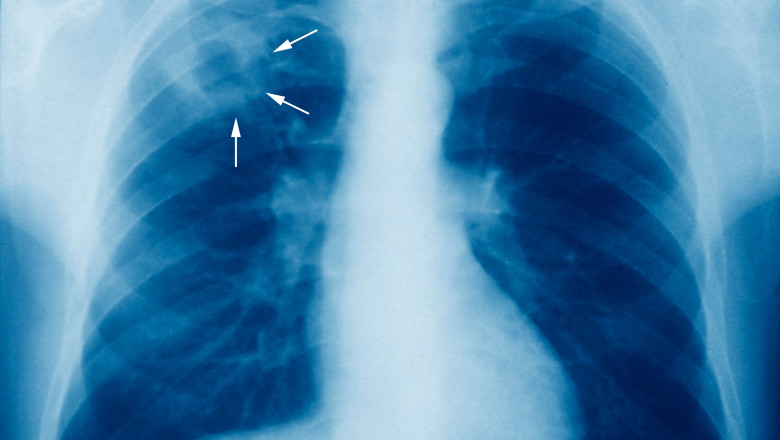

În cele 53 de ţări din regiunea OMS Europa, care acoperă şi Asia Centrală, aproximativ 230.000 de persoane au contractat tuberculoză, o boală cauzată de o bacterie ce atacă în principal plămânii - acest total rămânând totuşi în scădere în raport cu anii precedenţi.

În plus, prevalenţa tuberculozei rezistente la medicamente a crescut de asemenea pe scară largă, întrucât o treime din cazurile diagnosticate au fost cazuri de tuberculoză rezistentă la Rifampicină în 2021.